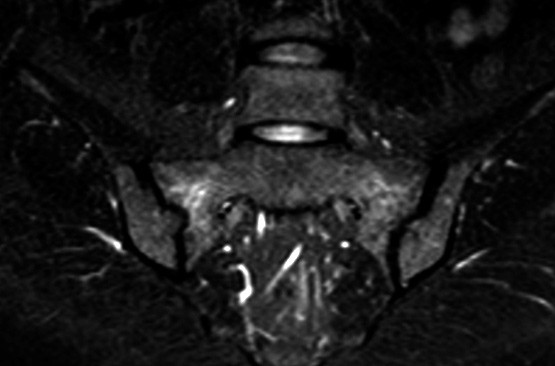

The woman then gradually developed pain extending from the lower back to both gluteal regions. Blood tests revealed normal calcium, low phosphate and elevated ALP levels, PTH in the upper normal range, normal 25-OH vitamin D and 1,25-(OH)2 vitamin D values. MRI scans (STIR sequence) detected high signal changes in both sacral wings and later also on the ileal side, indicating substantial bone oedema (left image). There were radiolucent lines in the sacral wings which raised suspicion of bilateral insufficiency fractures. Full body scintigraphy showed increased uptake in the anterior section of the frontal bone on both sides of the midline, in several ribs, both sacroiliac joints and proximally in the left tibia.